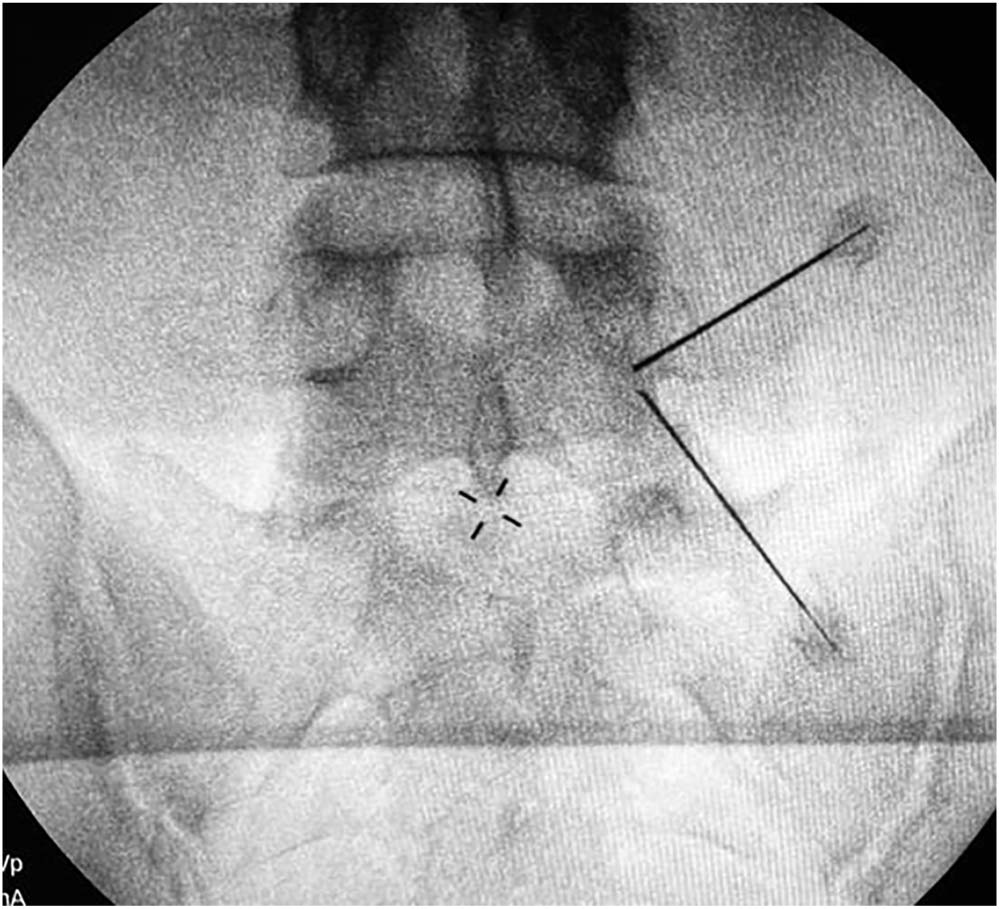

在C型透视的正位片上,标记相应节段的椎间盘上下界限和上下椎弓根。

该团队选择的Docking Point位于椎板的峡部。第一个切口与横突相对应,第二个切口位于尾端约3厘米处。通道切口在距离椎弓根外侧缘2-3cm的范围内进行。扩张阶段也应通过钝性解剖多裂肌来创建Son's空间。